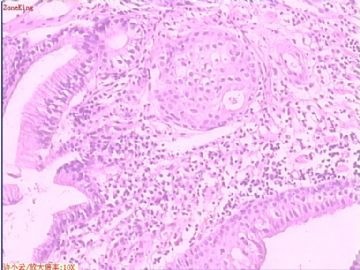

贲门息肉?

姓    名: ××× 性别:  女 年龄:  53

简要病史:  胃镜见,食道下段齿状线上可见一圆形隆起,有蒂,表面光滑,大小0.5X0.5X0.3cm.

各位老师,胃粘膜处出现的鳞状上皮有问题么?

• 贲门息肉?图1

图1

正好是齿状线腺鳞交界处粘膜

鳞状上皮没大问题,可能受炎症影响,稍有增生.

没有发现恶性证据,小心点儿可以拖个尾巴,譬如伴轻度异型增生。

本帖最后由 于 2009-11-21 09:51:00 编辑   谢谢各位老师指点,最终诊断为:贲门慢性炎症,伴局灶细胞轻度异型增生。